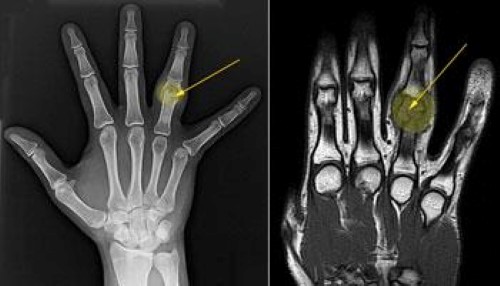

В редких случаях остеобластомы формируются на костях пальцев рук и ног, в местах прикрепления сухожилий. Такая локализация затрудняет работу сустава пальца или всей кисти. Даже небольшие опухоли в этой области могут вызывать дополнительные симптомы, такие как боль, жжение, воспаление кожи и атрофию мышц.

Перед назначением лечения врачам необходимо исключить злокачественные опухоли костей, которые могут проявляться схожими симптомами. Для точной диагностики проводятся внешний осмотр, анализ жалоб пациента и ряд дополнительных исследований, включая:

- Компьютерную томографию (КТ);

- Магнитно-резонансную томографию (МРТ);